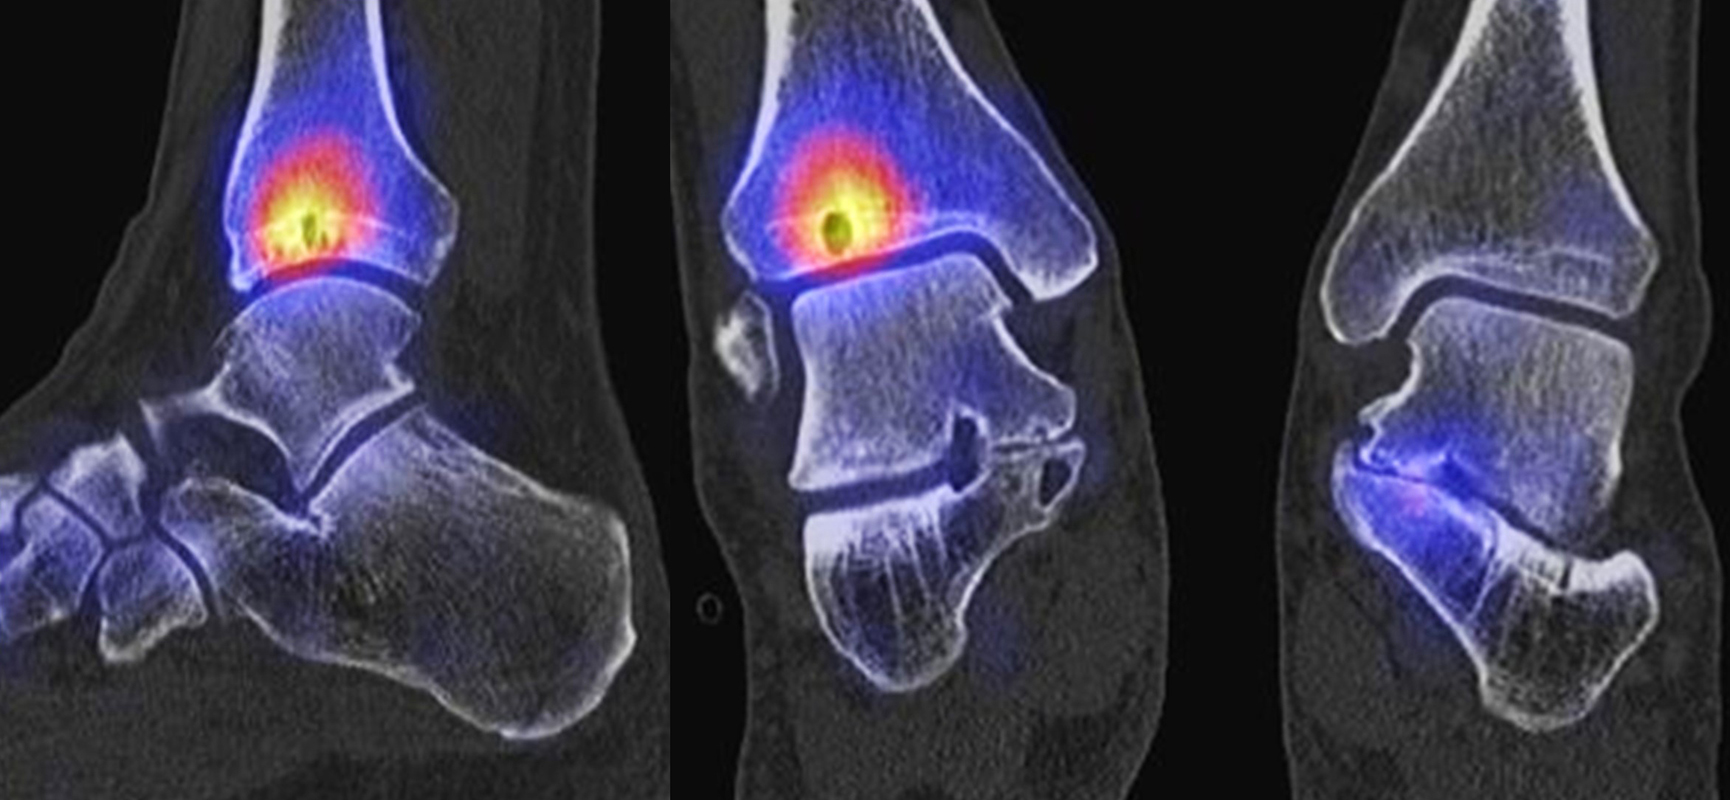

Die Abbildungen 4.2.a bis d zeigen den typischen Aspekt einer talacalcanearen Coalitio. Es besteht nur eine linksseitige, symptomatische Coalitio talocalcaneare (4.2.a und c); das 35 Tage zuvor angefertigte MRT zeigt keine auffälligen Signalveränderungen (4.2.b und d).